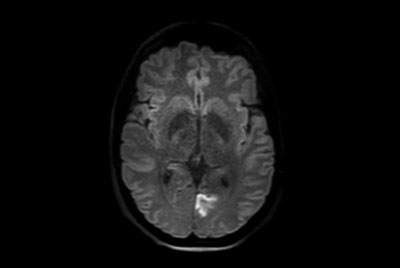

Brain lesions with computed DWI

Brain infarction

Brain small infarction